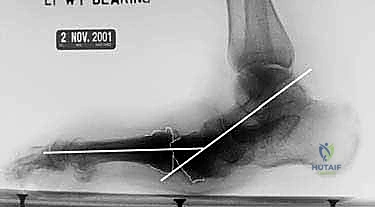

2. الأشعة السينية الحاملة للوزن (Weight-bearing X-rays): لتقييم الانهيار العظمي.

يتم استخدام أسلاك توجيهية (Guide Wires) يتم إدخالها تحت توجيه الأشعة السينية المباشرة (C-arm) من خلال عظام مشط القدم، مروراً بمفاصل منتصف القدم، وصولاً إلى عظام الرصغ (مثل العظم الزورقي أو الكاحل). بعد التأكد من المسار الصحيح، يتم استخدام مثقاب خاص، ثم تُدرج المسامير المحورية الصلبة (غالباً مسامير بقطر 6.5 مم أو 7.0 مم) لضغط المفاصل وتثبيتها بقوة هائلة.